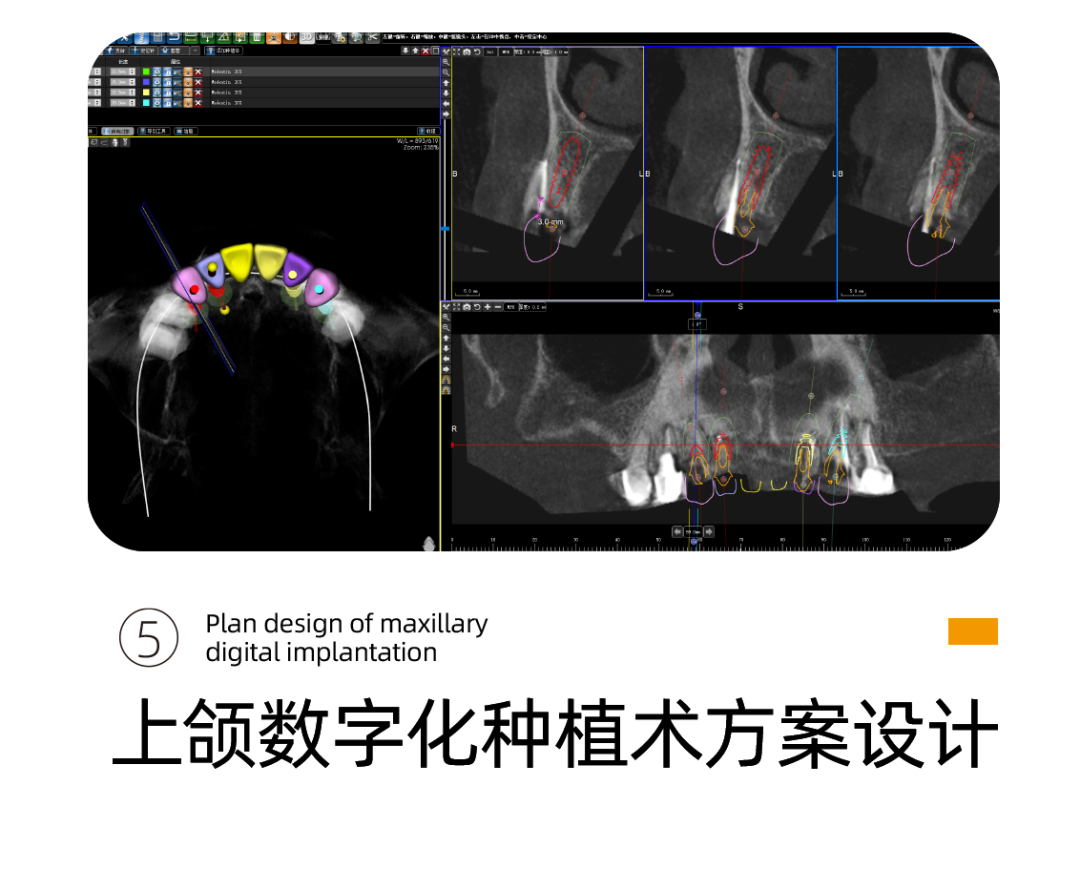

针对阿姨的情况,李雪松院长为阿姨指定全套的数字化种植方案。

什么是UNIC数字化种植方案呢?

其实就是借助Sirona CBCT全景影像信息和相关修复信息为基础,借助数字化专业种植设计软件进行术前诊断和种植方案规划。

通过数字化种植手术导向模板,将术前制订的种植方案准确应用于种植手术和即刻修复的全过程,实现以修复为导向的牙种植修复。

换句话说,运用数字化种植技术就是让所有种植操作可以直观得看到,并且能够看得懂。

它的优势在于种植医生借助数字化设备可以真正实现以修复为导向的种植理念,并且实际运用到临床操作中,实现微创种植,不翻瓣,将创口降到最低。

全数字化导板设计会依靠自身数字化的精确定位和微创特点,大大减少失误操作,提高种植手术的精准度。